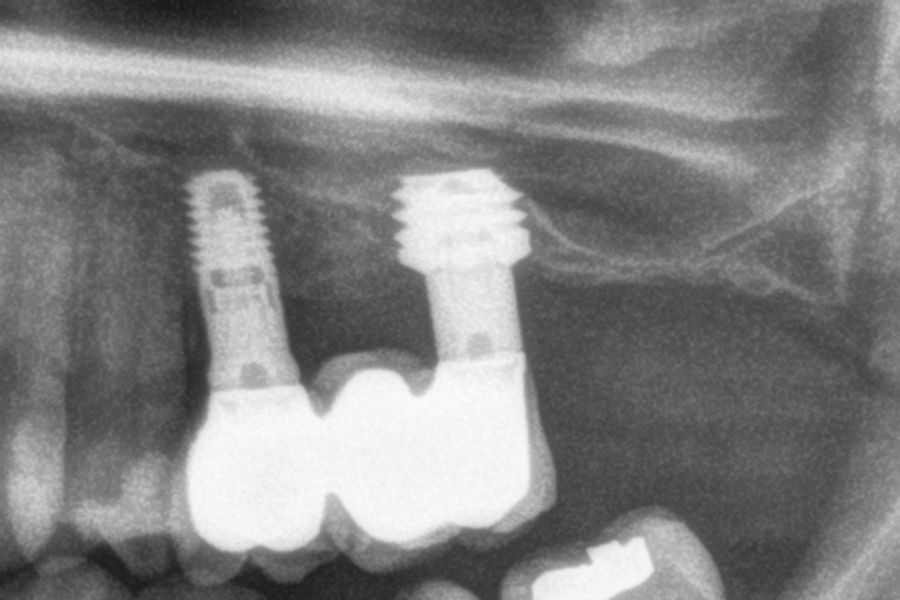

En las Figuras 7- 13 se muestra uno de los casos incluidos en el estudio.